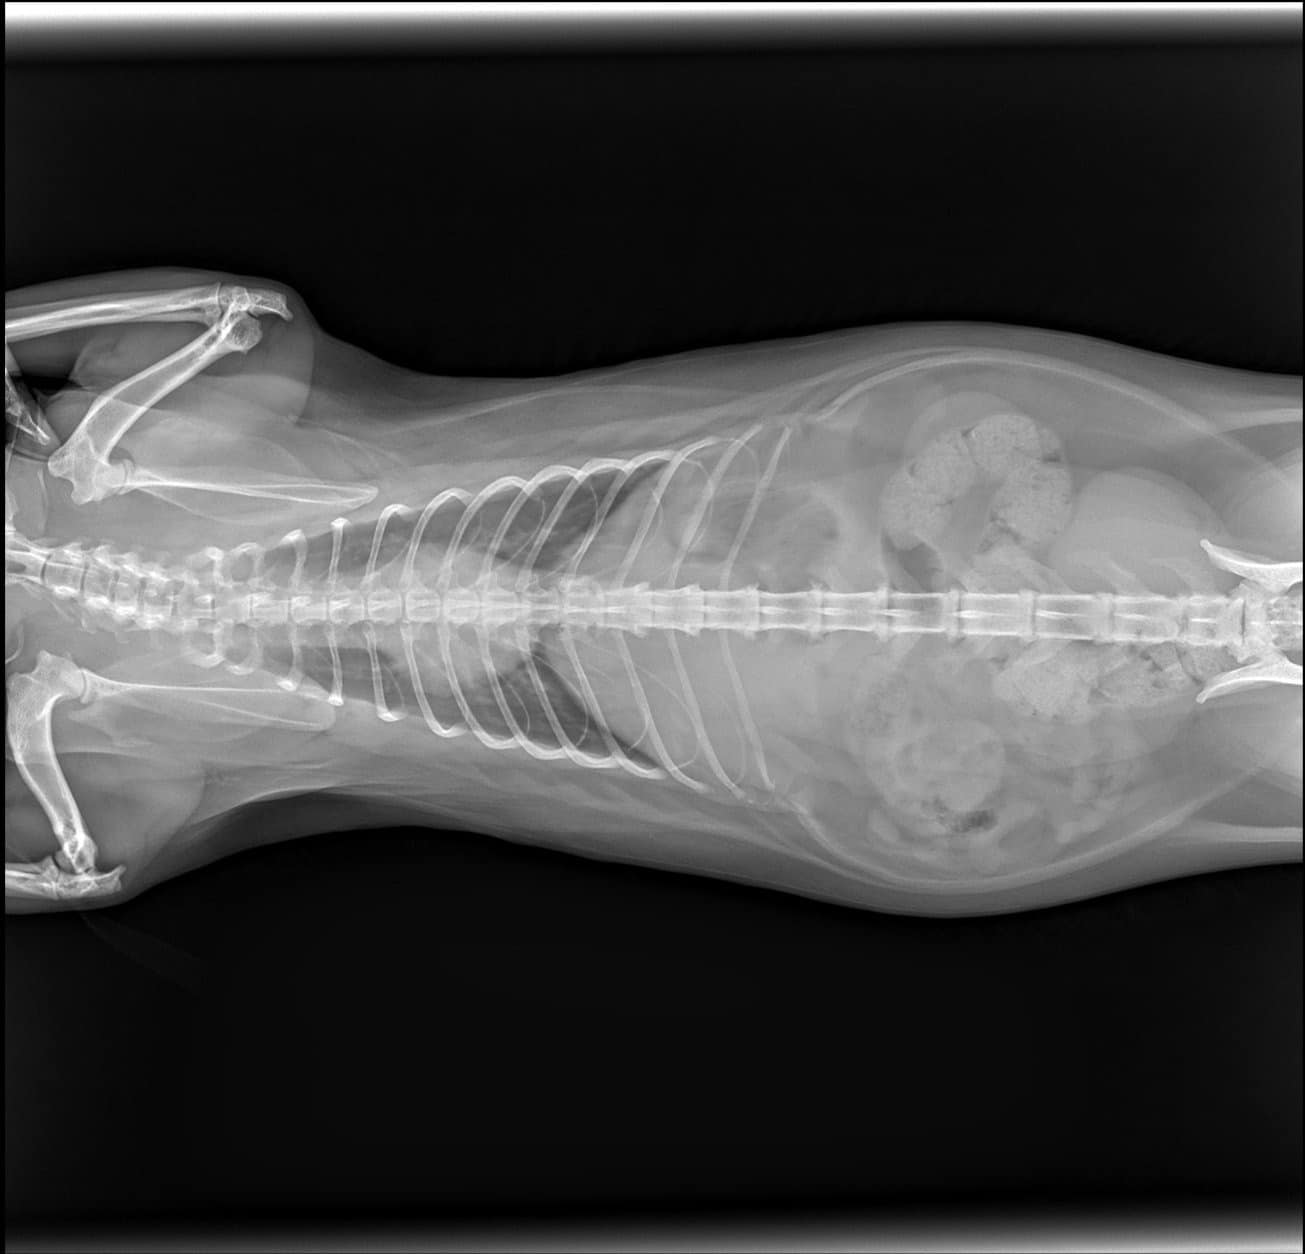

ทั้งนี้เมื่อตรวจสอบพบว่า น้องแมวอยู่ในสภาพตกใจเล็กน้อย แต่ไม่ได้บาดเจ็บหนัก โดยเจ้าตัวถูกล็อคเอาไว้เหมือนคนที่โดนจับได้ว่าทำผิด เนื้อตัวสะอาดสะอ้าน เมื่อนำไปเอ็กซเรย์ไม่พบอะไรผิดปกติ นอกจากเล็บที่ฉีกไปเล็กน้อย ในขณะที่ชาวเน็ตแห่แซวภาพเอ็กซเรย์เมื่อพบว่าในท้องแมวอ้วนมีอึแน่น